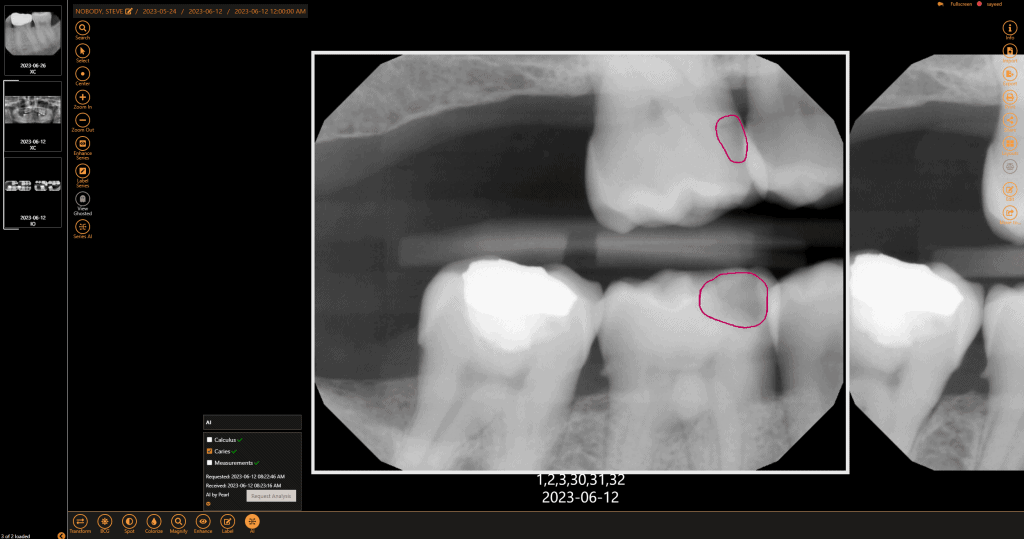

Get a second opinion to quickly detect decay, identify tartar buildup, and assess bone levels, ensuring a more accurate diagnosis of periodontal disease.

Within minutes, have more data than ever to guide and support your diagnosis with the patient chairside. AI makes it easier to visualize the areas of concern so patients can make a more informed decision.

Submit claims with greater confidence when the diagnosis is supported by quantified data.